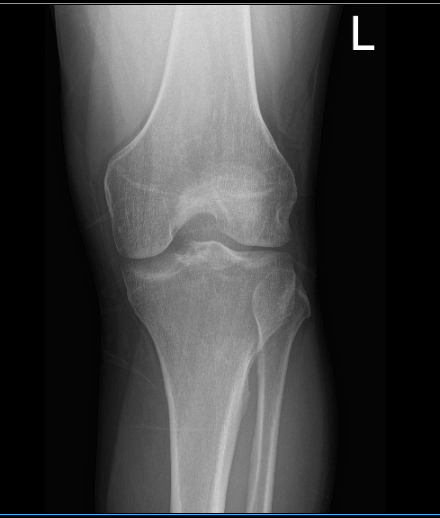

Patient is here with complaints of left knee pain. He is 26 year-old and currently employed as an electrician. He hurt his knee three months ago and is unsure exactly how, maybe he twisted it accidentally. He is not able to bend or extend the knee and is hopping with a limp and not able to bear weight on the foot. He is here with X-rays on his left knee.

X-ray results showed that there is mild lateral compartment joint space narrowing. We discussed treatment options on his condition including Physical Therapy, MRI, Injection and Surgery. We agreed to go with 3 tesla MRI left knee, he also agreed to start the PT and continue Rest/Ice/Compression/ Elevation Therapy.